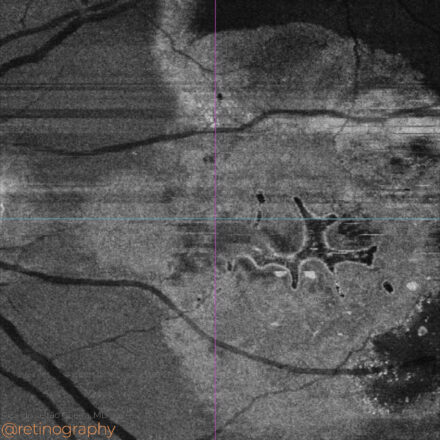

AMD: Outer retinal tubulations

77yo

77yo In age-related macular degeneration (AMD), outer retinal tubulations (ORT) can present unique patterns on en-face OCT, often resembling intraretinal fluid (IRF), leading to potential misdiagnosis. In the presented case, en-face imaging shows ORT as hyporreflective interconnected branching networks extensions surrounded by a hyperreflective borders, while dark areas without hyperreflective borders […]